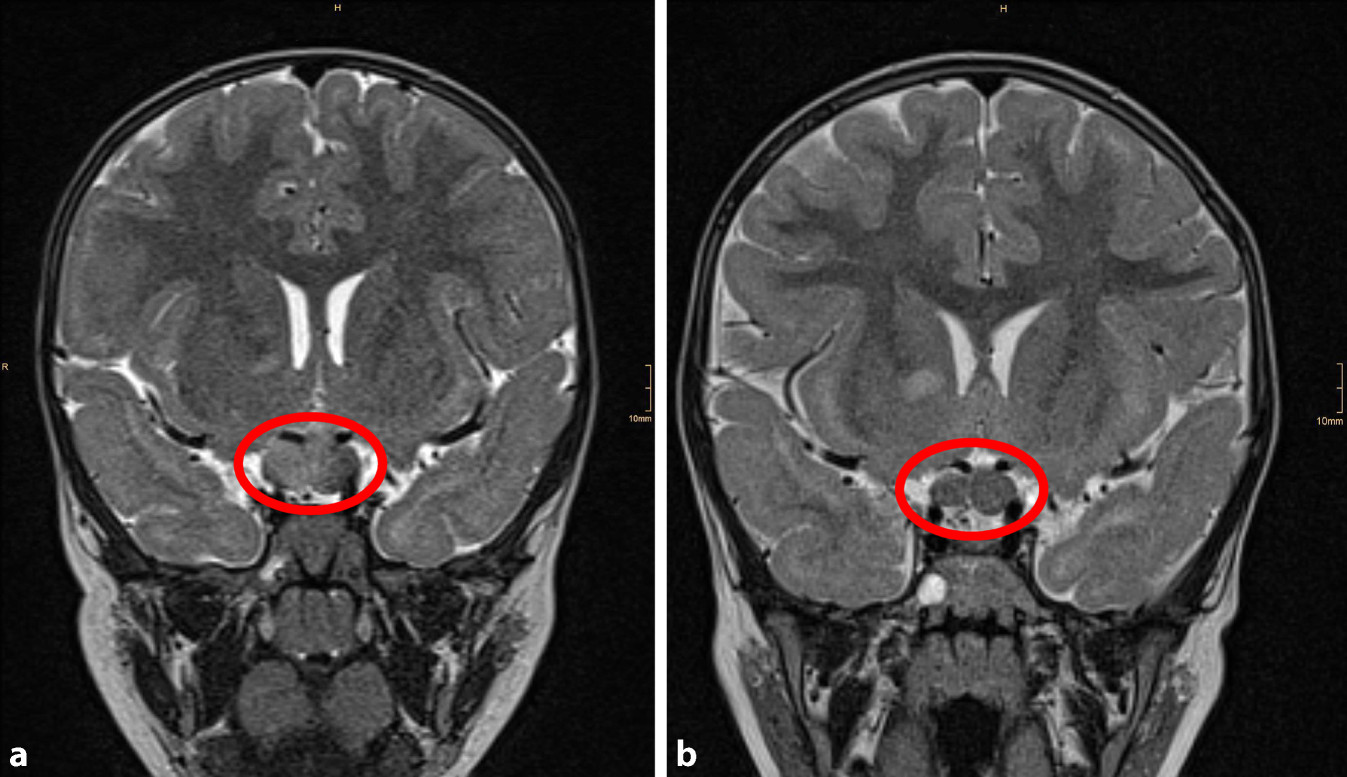

Abb. 2

MRT von Patient 1 a vor und b nach 18 Monaten Chemotherapie (Markierung: Tumorausdehnung im Chiasma opticum). (© A. Azizi)

Alexej (Name geändert) wurde im 6. Lebensmonat am NF Kinder-Expertisezentrum der Med. Univ. Wien vorgestellt, nachdem beim Kinderarzt Café-au-lait-Flecken auf der Haut aufgefallen waren. Die Eltern selbst wiesen keine Symptome einer NF1 auf, eine genetische Untersuchung aus dem Blut konnte schließlich den Verdacht auf Neurofibromatose Typ 1 (NF1) sichern. Es erfolgten konform der Leitlinien regelmäßige Augenkontrollen aufgrund des bei NF1 erhöhten Risikos auf Sehbahngliome [2], und im 2. Lebensjahr erfolgte eine an unserem Zentrum routinemäßige MRT-Screening-Untersuchung. In dieser zeigte sich ein ausgedehntes, linksseitig betontes Optikus/Chiasma-Gliom. Es wurde mit der Familie besprochen, dass es sich hierbei um einen Tumor der Sehbahn handelt, der zwar biologisch gutartig ist, aber zu einer erheblichen Einschränkung der Sehleistung bis hin zur Erblindung führen kann. Zu dem Zeitpunkt konnten bei dem Patienten aufgrund der altersbedingten schlechten Compliance noch keine zuverlässigen Augenuntersuchungen durchgeführt werden, sodass eine Visusbestimmung nicht möglich war. Es erfolgten kurzfristige MRT-Kontrollen alle 3 Monate, in denen sich im Laufe des nächsten halben Jahres eine Größenzunahme des bekannten Glioms zeigte. In der Zwischenzeit konnten auch binokuläre Augenuntersuchungen durchgeführt werden, in denen sich eine Abnahme des Visus im Verlauf zeigte. Der Patient wurde in unserem interdisziplinären pädiatrisch neuroonkologischen Tumorboard diskutiert, in welchem die Indikation für eine Chemotherapie, gemäß internationalen Standards, mittels Carboplatin und Vincristin gestellt wurde. Es erfolgten ausführliche Gespräche mit der Familie über die Notwendigkeit einer Behandlung, die Eltern lehnten die Chemotherapie zu diesem Zeitpunkt jedoch ab, da sie im Alltag kein Problem bemerken konnten. Im Laufe der nächsten Monate war auch eine seitengetrennte Augenuntersuchung möglich, und es zeigte sich, dass der Visus (dezimal) auf dem linken Auge nur 0,3 betrug, während das rechte Auge einen Visus von 0,63 aufwies, und somit eine klare Seitendifferenz und eindeutige Sehbeeinträchtigung vorlagen. Nachdem den Eltern erneut der Ernst der Situation dargelegt wurde, stimmten sie schließlich der Behandlung ihres nun bald 3‑jährigen Kindes zu. Die Therapie führte zu einer deutlichen Reduktion der Tumorausdehnung (Abb. 2), leider kam es jedoch im weiteren Verlauf zu einem Fortschreiten des Sehverlustes ohne wesentliche Größendynamik des Tumors. Es folgten daher noch zwei weitere medikamentöse Behandlungen, eine Verbesserung des Visus konnte jedoch nicht mehr erreicht werden. Dies deckt sich leider mit den Daten einer europäischen Studie, die darauf hinweisen, dass ein früher Therapiebeginn die Chancen auf eine Sehverbesserung erhöht [3]. Alexej ist nun 8 Jahre alt und weist mit einem Visus von rechts 0,16 und links 0,03 eine hochgradige Sehbeeinträchtigung auf. Er besucht eine Integrationsklasse und ist auf diverse Hilfsmittel des Blindeninstituts angewiesen, um dem Schulunterricht zu folgen, z. B. einer speziellen Kamera, die ihm hilft, die Schrift auf der Tafel lesen zu können.